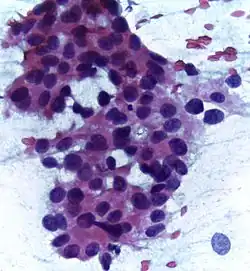

![]() | Infiltrative ductal carcinoma | Atypical cells with moderate amount of eosinophilic cytoplasm and round to oval dark nucleus with moderate pleomorphism (Papanicolaou, 400X) | Category: Histopathology of invasive carcinoma of no special type | invasive breast carcinoma |